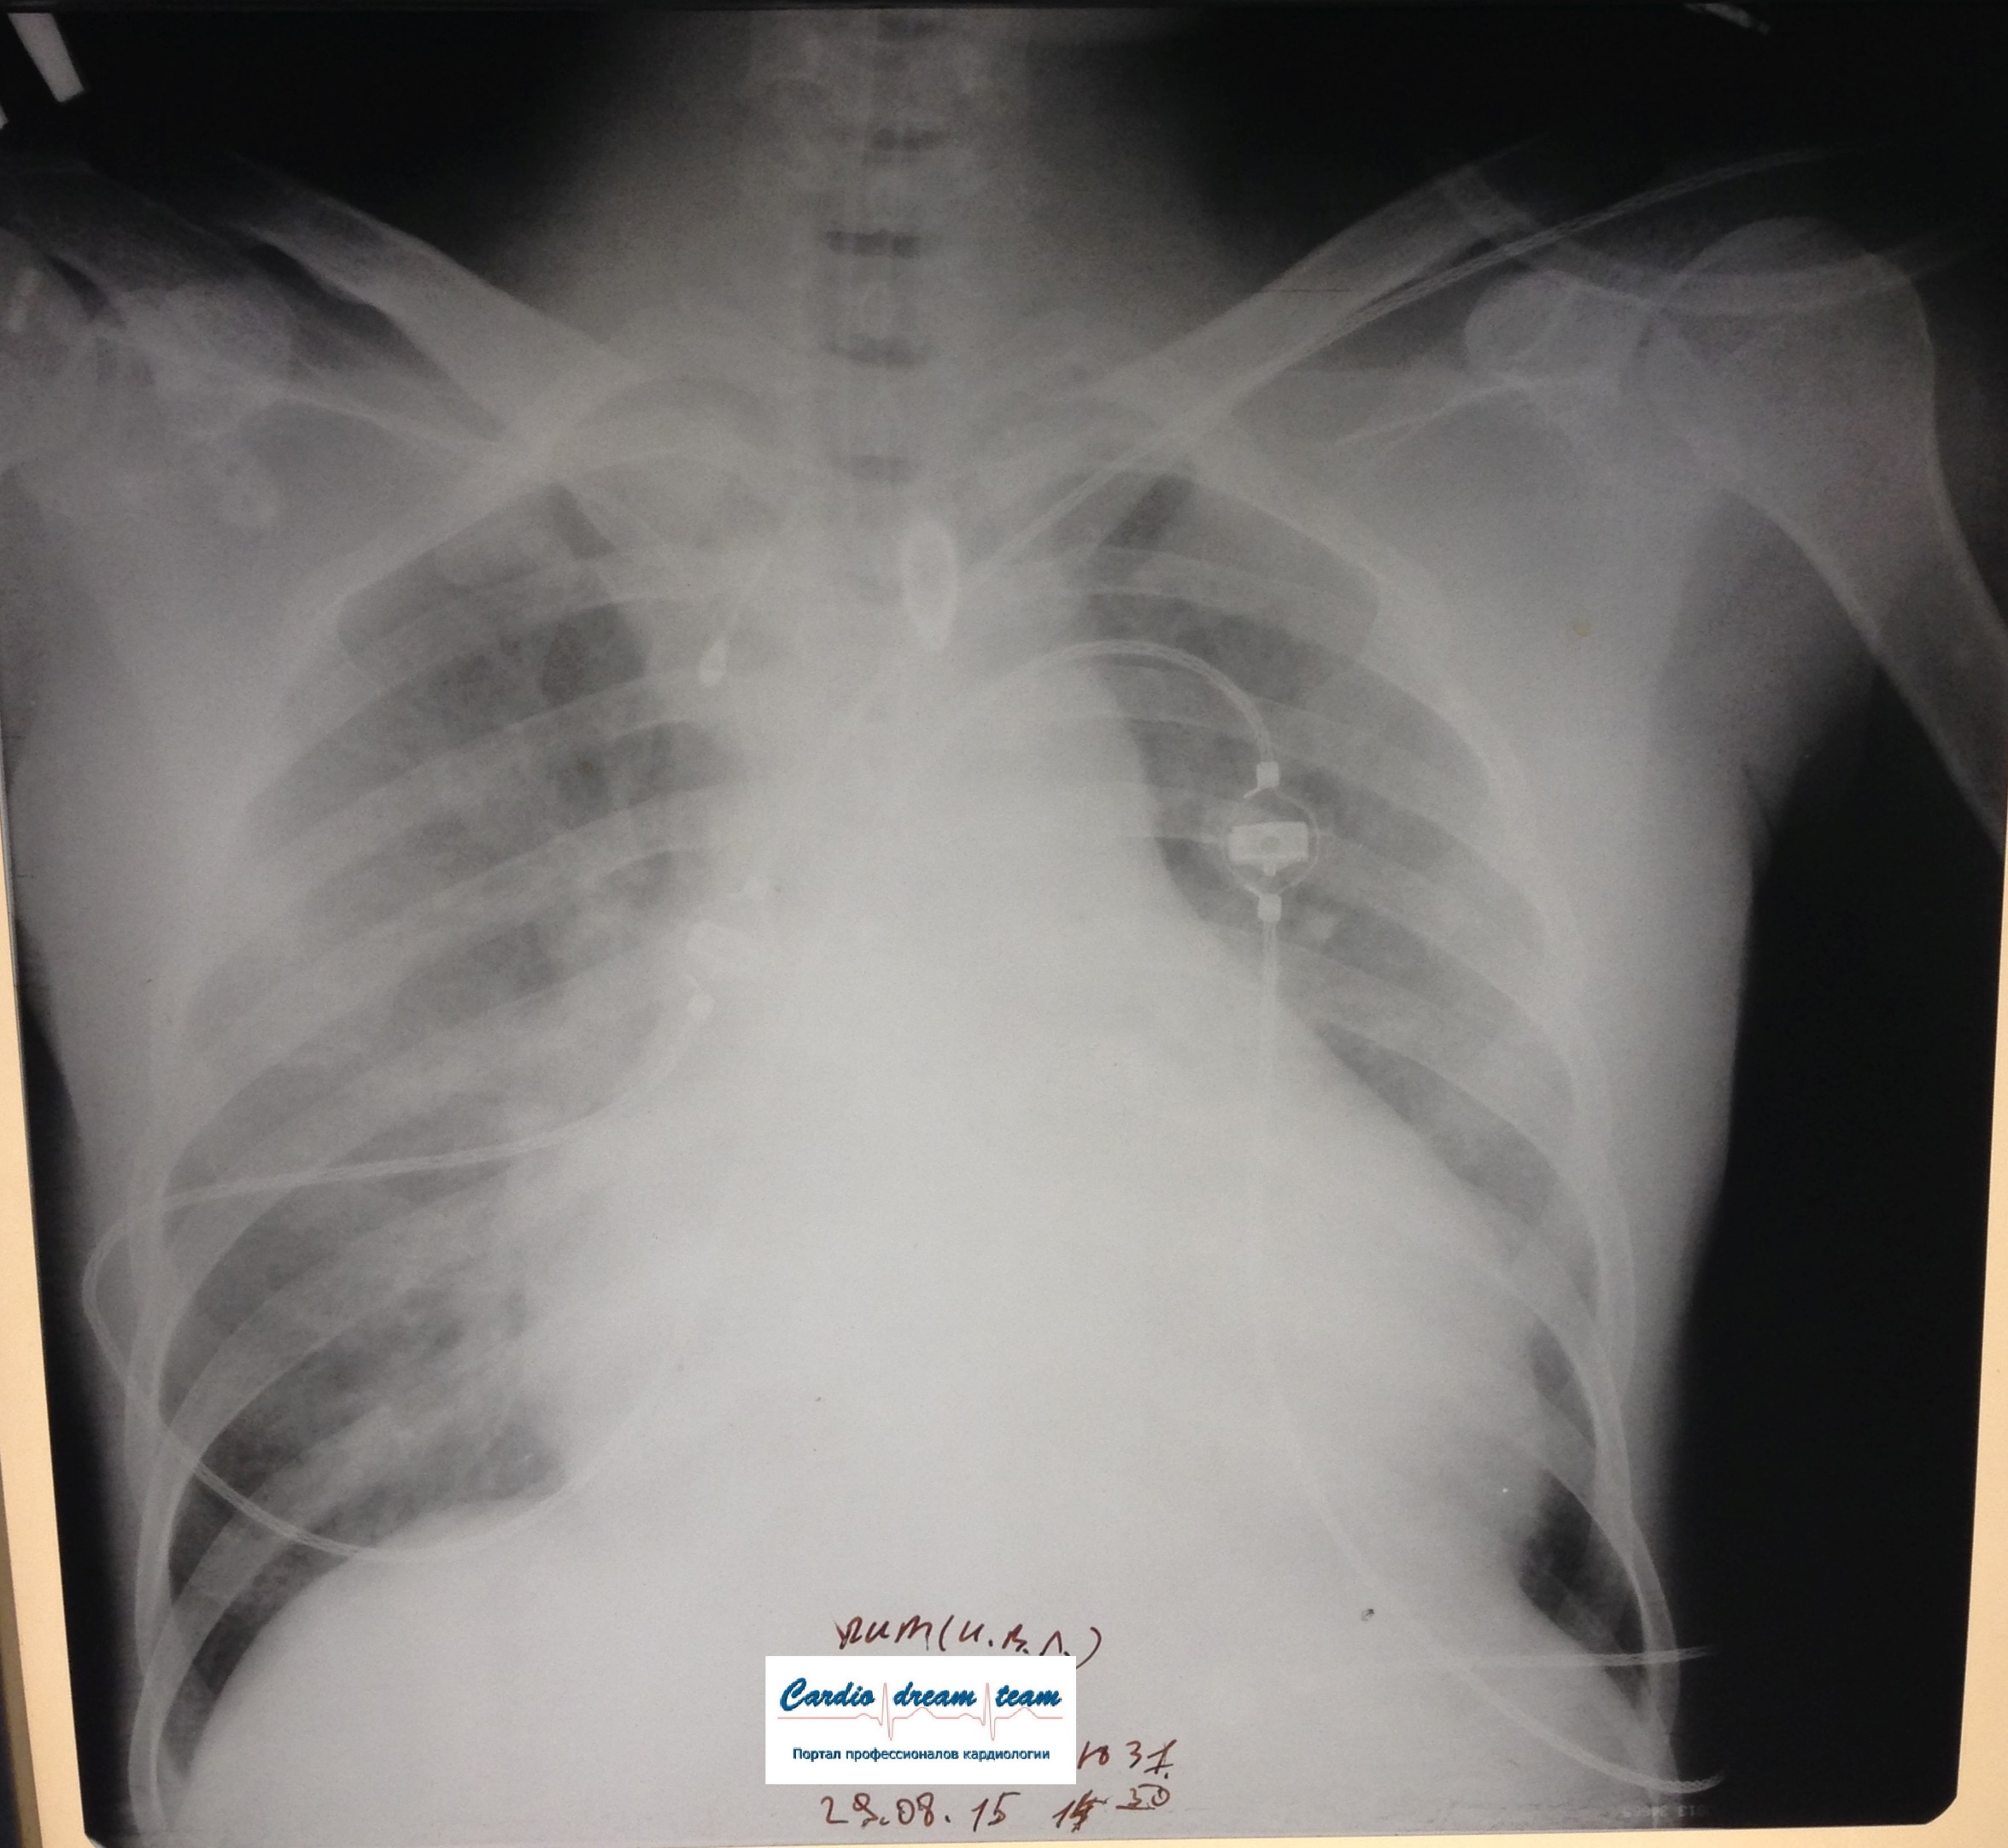

Возникновение и динамика вентилятор - ассоциированной пневмонии.

Вложения:

1-.jpg

1-.jpg [ 713.01 KiB | Просмотров: 53560 ]

2-.jpg

2-.jpg [ 759.1 KiB | Просмотров: 53560 ]

3-.jpg

3-.jpg [ 754.54 KiB | Просмотров: 53560 ]